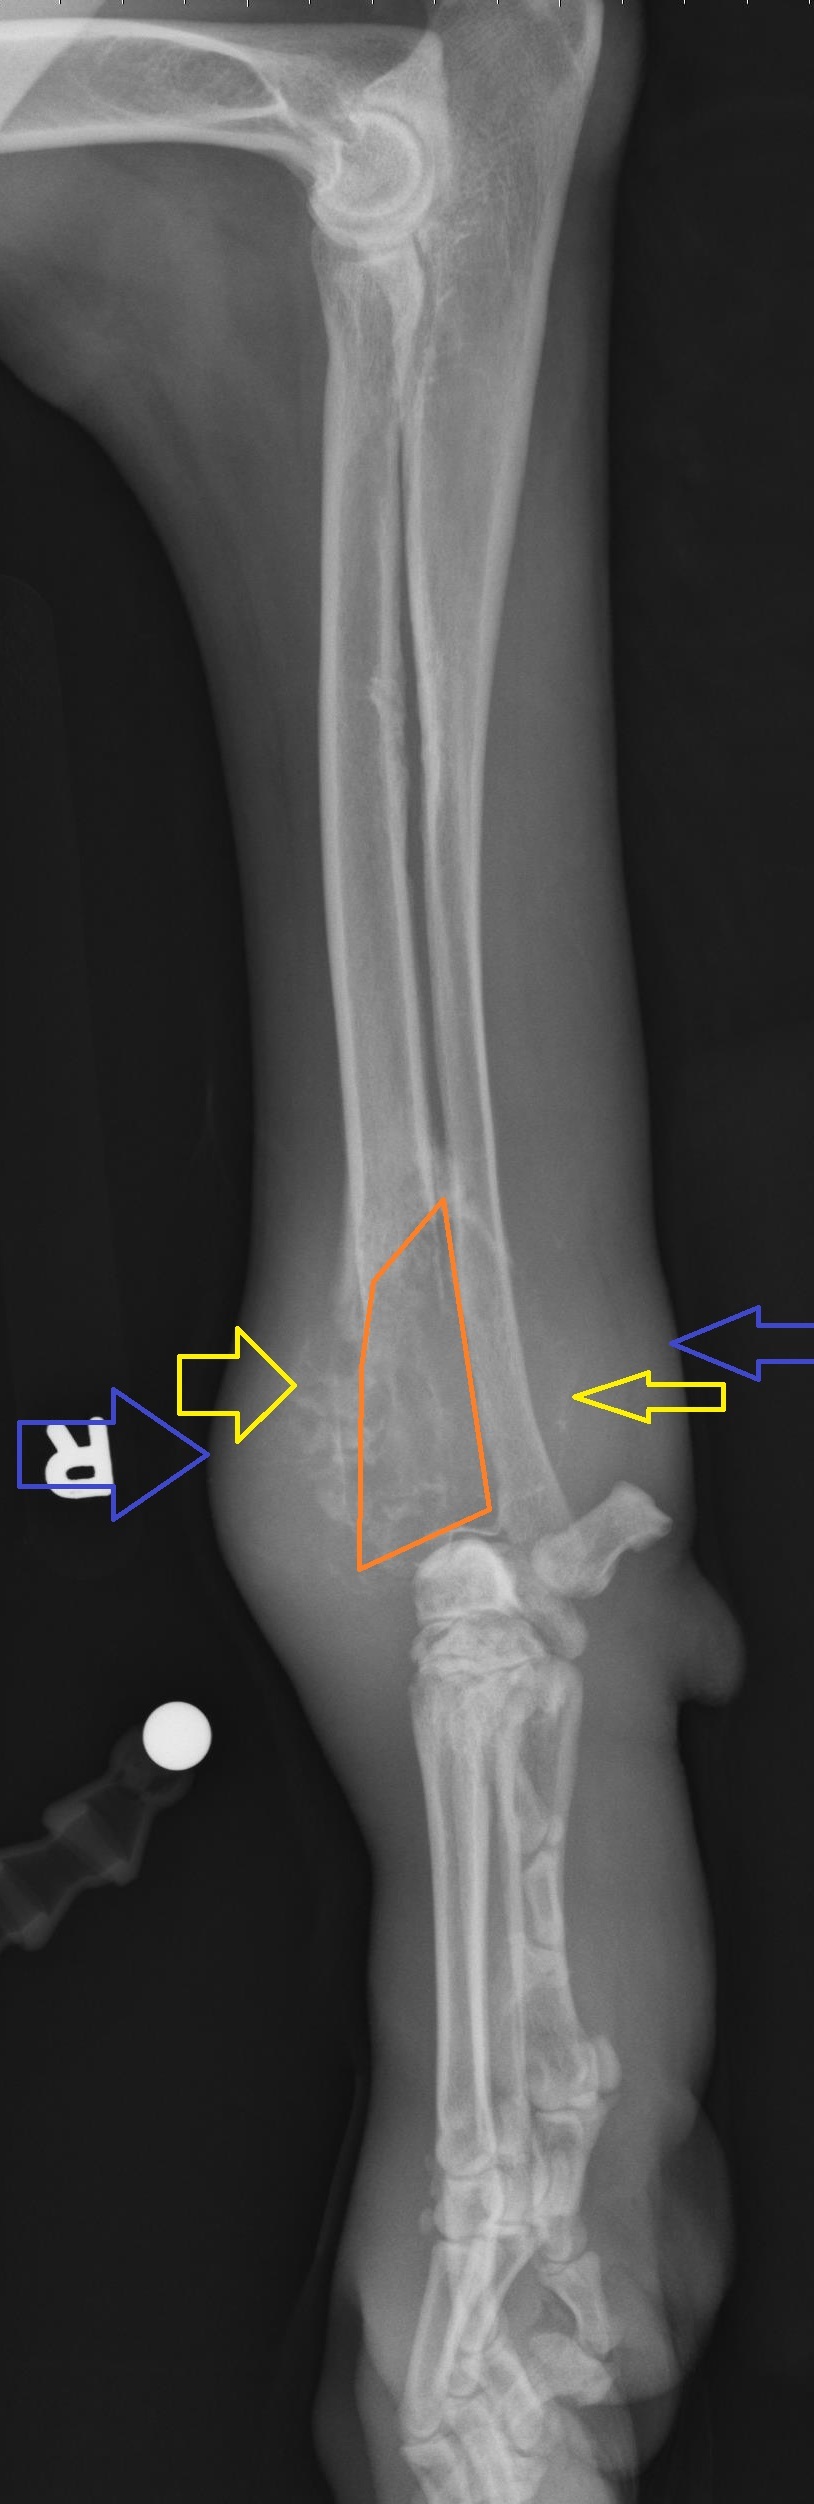

A 6-year old male neutered Weimaraner presents for right forelimb lameness. Radiographs are shown below and show a mixed productive and destructive lesion affecting the right distal radius with accompanying soft tissue swelling. The lesion does not cross the joint. What is the most common primary bone tumor in the dog?

Osteosarcoma

The correct answer is osteosarcoma. Chondrosarcoma, fibrosarcoma and hemangiosarcoma can all be primary bone tumors but are much less common in dogs than osteosarcoma.

Annotations:

Yellow: Amorphous periosteal proliferation

Orange: Geographic lysis and expansile appearance of the mid-radius

Blue: soft tissue swelling